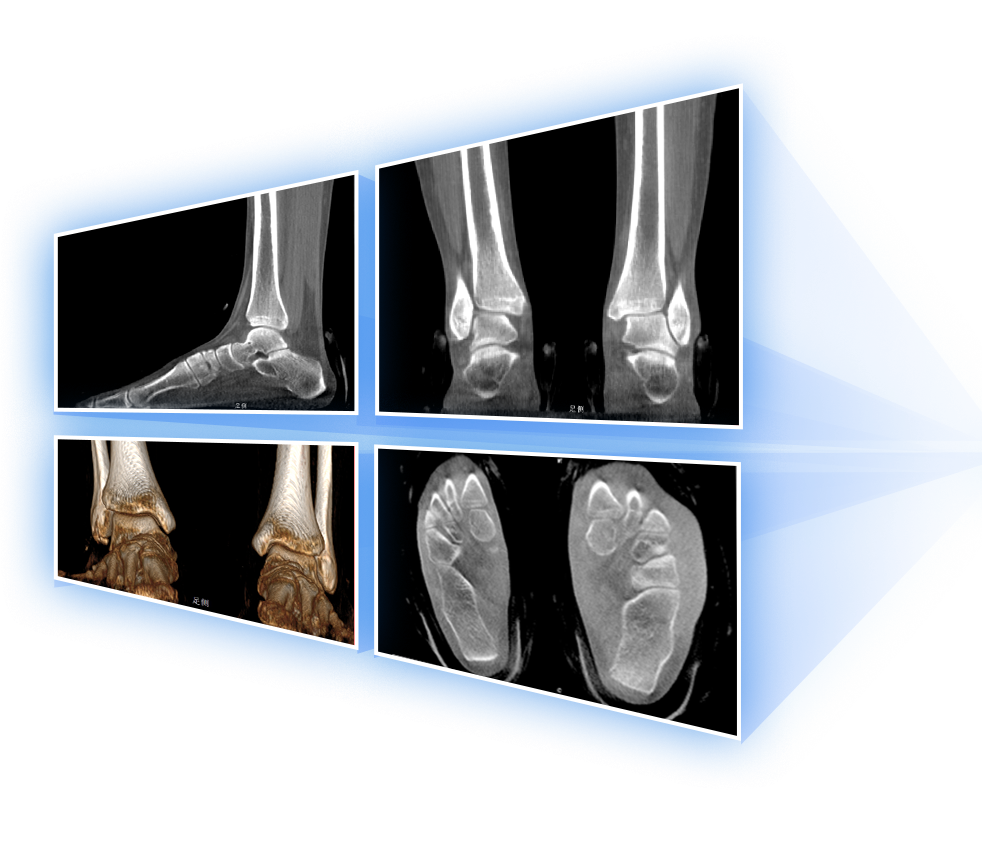

• 足踝

FOV最大350mm

支持双腿或双侧髋关节扫描 | 方便对比,降低漏诊误诊

FOV 250mm

FOV 350mm